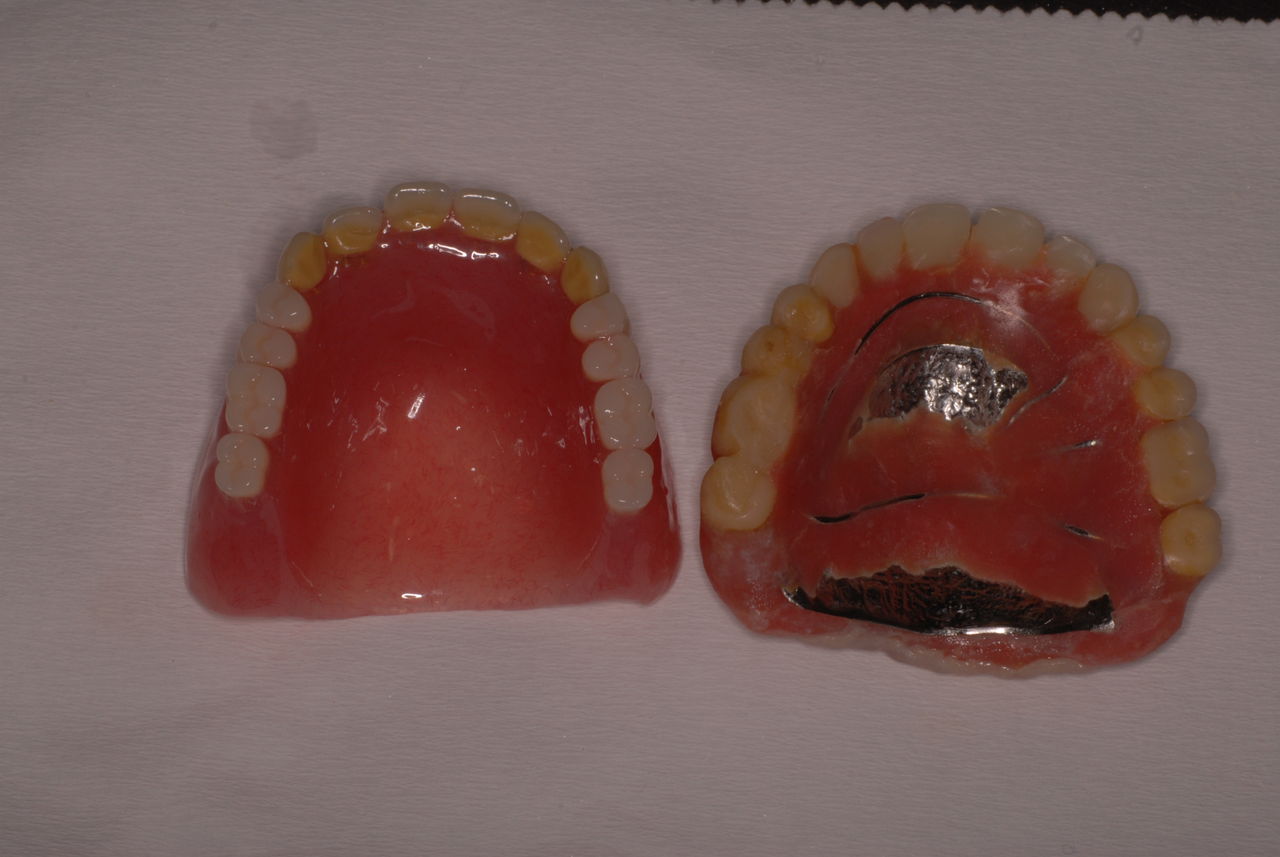

金属にもかかわらず適合が悪い為にプラスチックを重ね着した為に厚くなりしゃべりにくくなっていました。

かなり分厚い入れ歯です。

外注で完成させた入れ歯です。

違いは歯の位置です。あまりに外側で噛むと動くから噛めないのです。